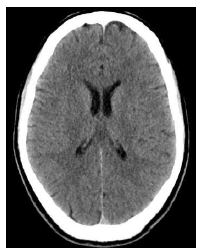

Um homem de quarenta anos de idade, em situação de rua, foi levado pelo SAMU ao hospital, devido a rebaixamento do nível de consciência em via pública. Na admissão, foram verificados sinais de desnutrição importante, hálito etílico e glicemia de 25 mg/dL. O paciente foi tratado exclusivamente com glicose endovenosa, evoluindo com melhora do nível de consciência e surgimento de confusão mental, nistagmo e ataxia.

Foi realizada uma tomografia de crânio, cujo resultado está representado abaixo.

Com relação ao caso clínico acima, assinale a alternativa que apresenta, respectivamente, o diagnóstico mais provável e o tratamento indicado ao paciente.